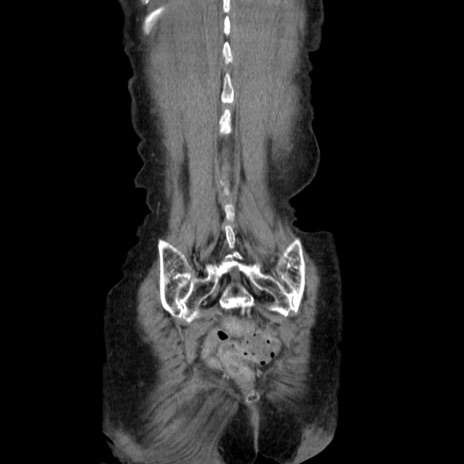

症例25(冠状断像)

横断像